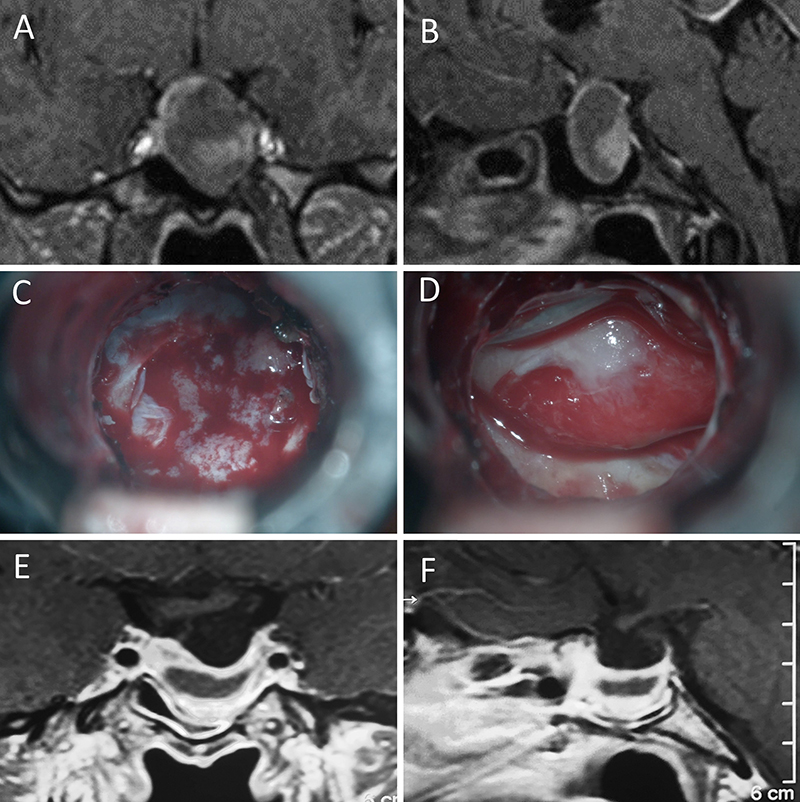

Figura 14: Prolactinoma en un hombre de 32 años. Sufrió un cuadro de apoplejía pituitaria durante su tratamiento con cabergolina. Fue intervenido quirúrgicamente, evolucionando con normoprolactinemia. A-B: RM preoperatoria; C-D: intraoperatorio; E-F: RM postoperatoria.

Figura 15: Prolactinoma en una mujer de 19 años. Cursó con cuadro de resistencia a la cabergolina. Se decidió tratamiento quirúrgico y evolucionó con remisión bioquímica. A-B: RM preoperatoria; C-D: intraoperatorio; E-F: RM postoperatoria.